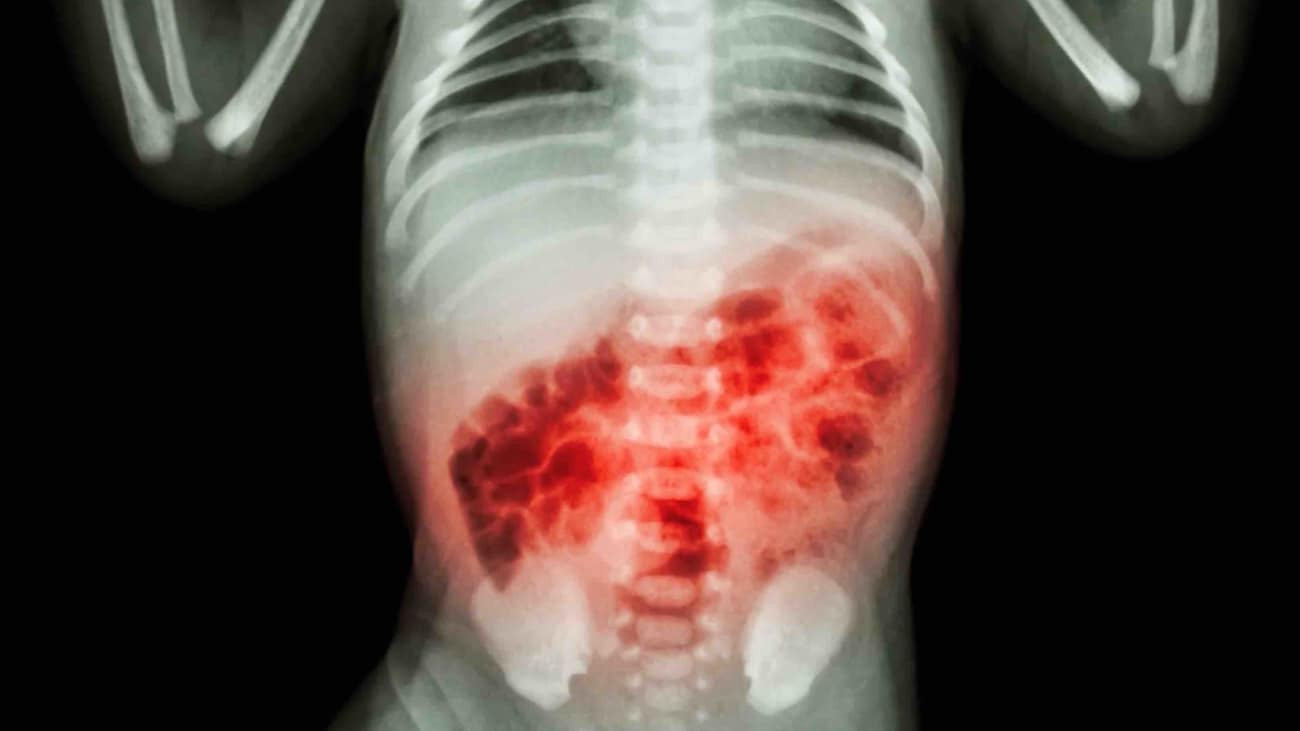

Enterokolitis Nekrotikans

Enterokolitis nekrotikans adalah penyakit serius berupa kerusakan dan kematian jaringan usus yang banyak mengenai bayi prematur